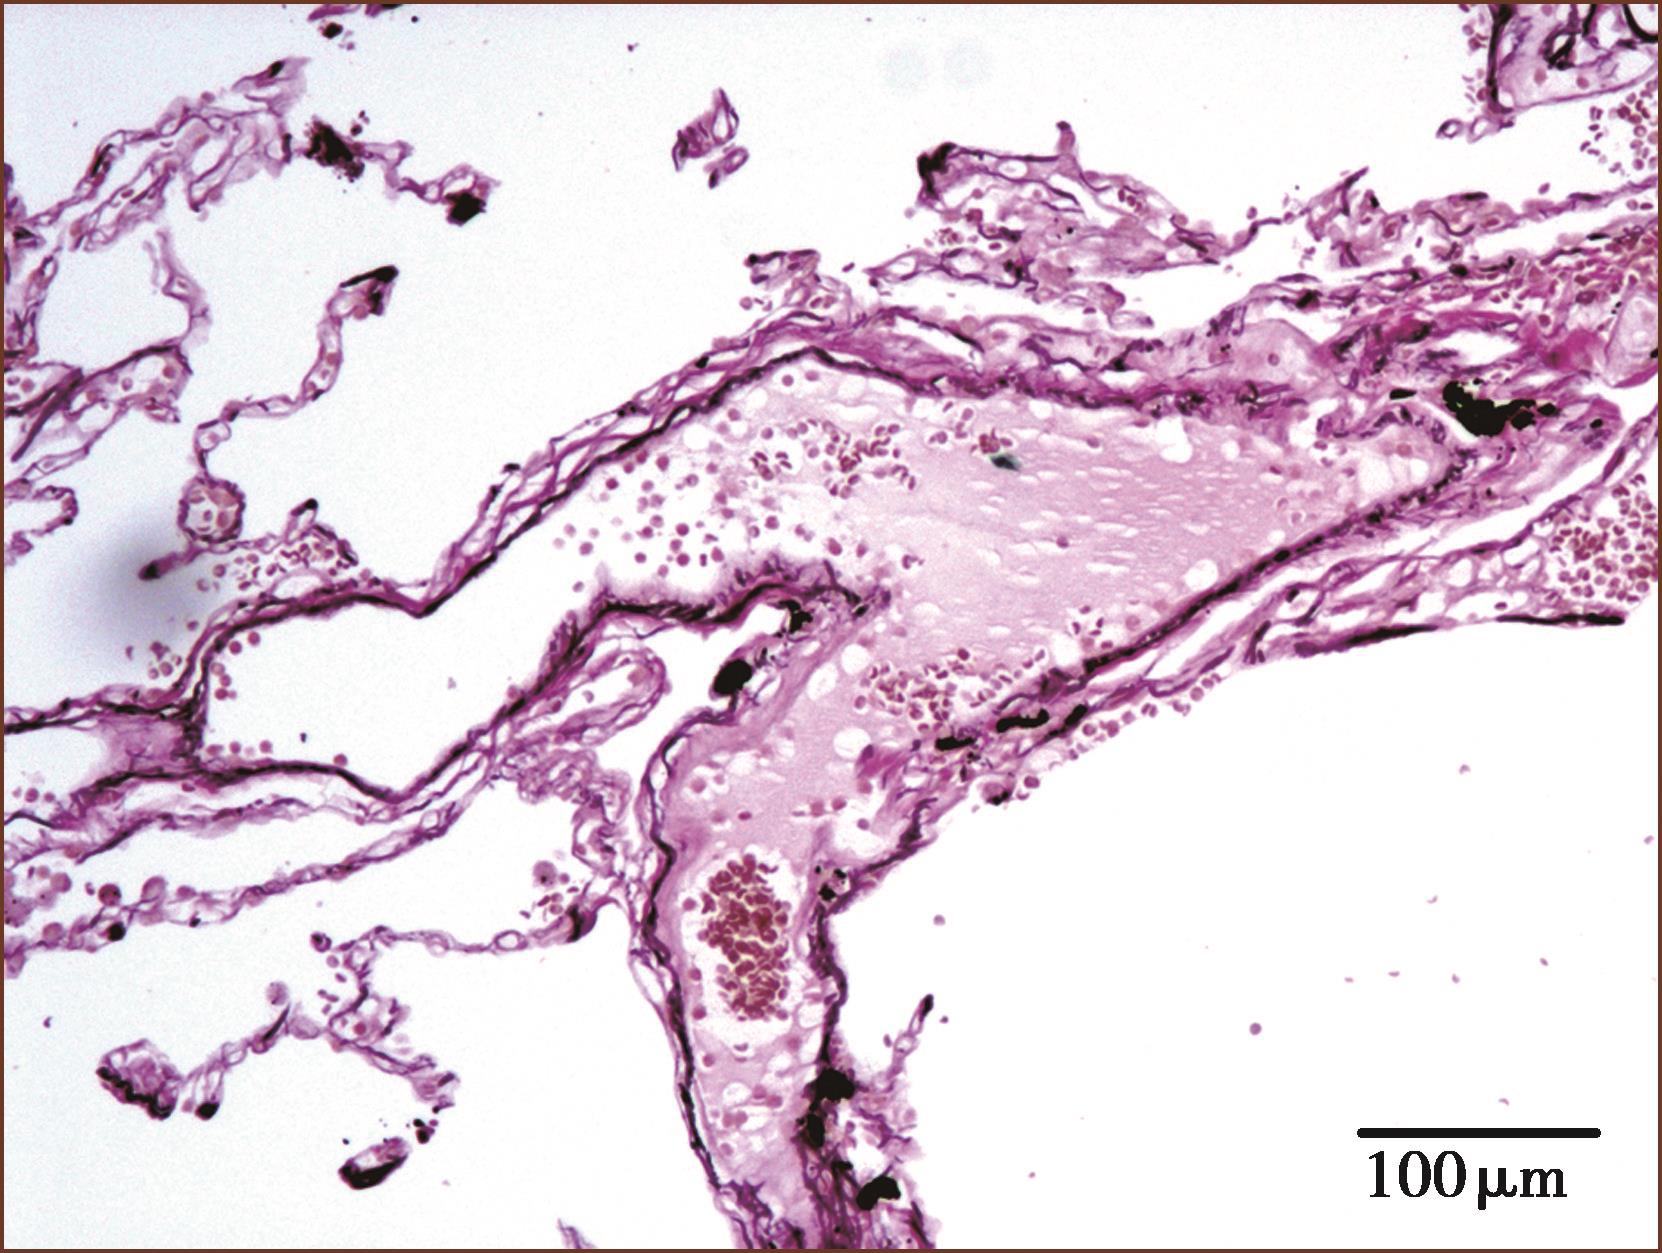

图1-3-5 肺内较大静脉,管壁薄,管腔较大(ET+VG染色,中倍放大)

图1-3-6 肺内细静脉,管壁结缔组织成分较多(ET+VG染色,中倍放大)